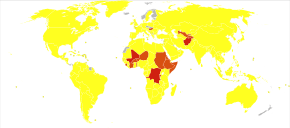

Hearing loss

Children with recurrent episodes of acute otitis media and those with otitis media with effusion or chronic suppurative otitis media have higher risks of developing conductive and sensorineural hearing loss. Globally approximately 141 million people have mild hearing loss due to otitis media (2.1% of the population).[48] This is more common in males (2.3%) than females (1.8%).[48]